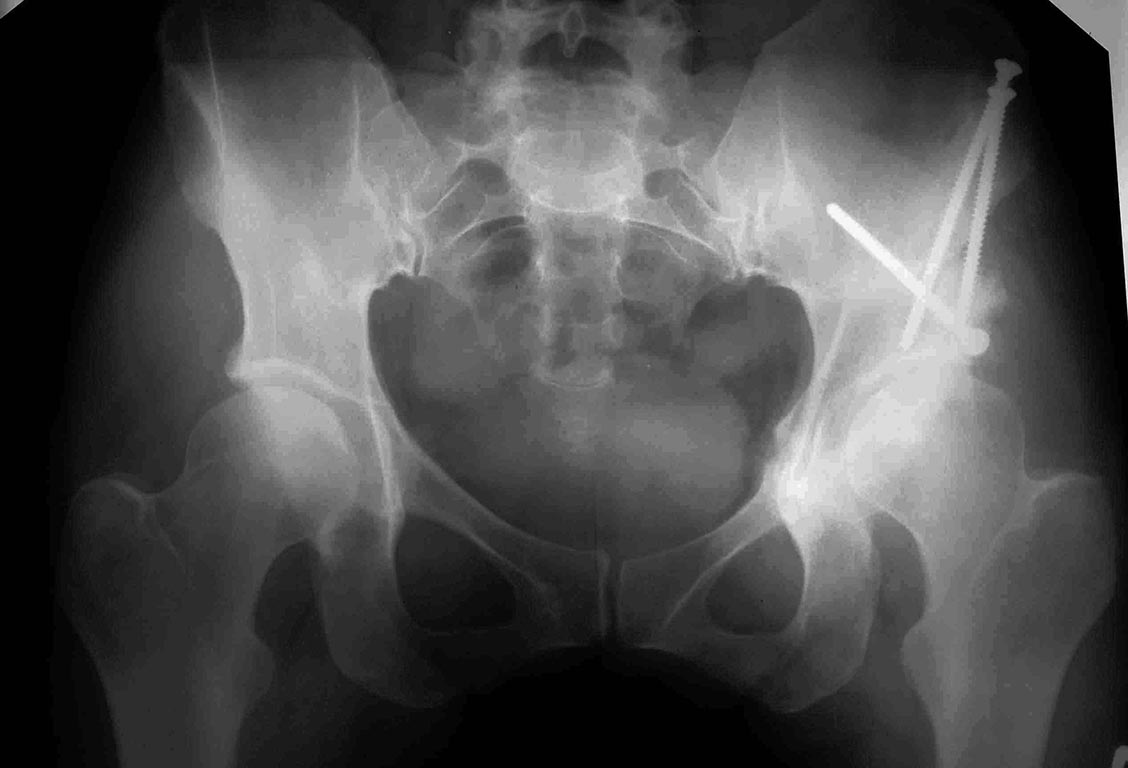

Пациентка 40 лет оперирована по-поводу дисплазии т/б сустава - ПАО, огромное спаибо нашим коллега из Н.Н., честно, без иронии. Сейчас 6 мес после операции, появилась боль, по тестам, похоже на импинджемент. Имеет ли смысл за ним гоняться? Или рекомендовать поверхностное или тотальное протезирование?PS Да, не все проекции выложил, это предварительный вопрос, сам опыта вмешательств при FAI не имею, потому спрашиваю совета. Если кто возьмется доделаю проекции и МРТ

А не поздновато оперировали? Там уже артроз, похоже, приличный был. Да и покрытие головки остается недостаточным.

Вы говорите о том, что остеотомия срослась. Но снимки не представляете. И о том, что имеются симптомы феморо-ацетабулярного синдрома. Но какие это симптомы - не перечисляете. Так дискутировать сложно. Известно, что рентгенологическими признаками, сопутствующими предполагаемому Вами состоянию, являются глубокая вертлужная впадина или форма шейки бедренной кости в виде "ручки револьвера". И еще уменьшенный шеечно-диафизарный угол. А здесь непокрытая полностью головка, обычная шейка, большой ШДУ. И выраженный артроз. Что же должно заставить думать о феморо-ацетабулярном импиджменте?

О ФАИ могут заставить думать клинические проявления, а кроме описанных Сергеем Юрьевичем рентгенологических признаков ФАИ причиной может являться ретроверсия впадины, проявляющаяся на рентгене "восьмеркой". Но по представленным послеоперационным рентгенограммам оценить ее, мягко говоря, сложно, края впадины прослеживаются нечетко. Кстати импдижмент стал изучаться усиленно после первых результатов ПАО, в случаях, когда операция сопровождалась гиперкоррекцией или потерей антеверсии в процессе позиционирования впадины. Возможно здесь тот самый случай - начало кривой обучения сложным операциям.

Зная нормальные значения углов, можно понять, насколько в результате операции удалось приблизиться к норме. Согласно моим замерам достигнуты физиологические значения угла Виберга (с 7,7 до 21,5) и наклона опорной поверхности(с 23,8 до 11). Хотя по-хорошему среди предоперационных снимков должна быть тоже обзорная проекция таза. Можно еще мерить процент погружения головки во впадину, индекс глубины впадины и другие индексы. Конечно, значения могут варьировать в разных руках, но так будет хотя бы не "на глаз", можете представить свои измерения и показать на сколько какой параметр изменился.

Успешность предшествовавшей ПАО весьма сомнительна (с позволения ув. Шведовченко Игоря Владимировича добавлю): угол Виберга (или LCEA, если Вам удобнее англоязычность) до операции в лучшем случае 14 градусов, после - 18 градусов по самым позитивным представлениям (при норме 26-35). Угол наклона крыши вертлужной впадины (Tonnis angle): до операции - 20 гр., после 13 гр. (норма 0-10).

Снимки в проекции "ложного" профиля показывают в большей степени передне-наружный отдел вертлужной впадины. И, если Вы говорите что там все "неплохо", то это как раз и может быть причиной проблемы на данный момент - передний импинджмент, как последствие ПАО.

Для принятия решения о тактике дальнейшего лечения и оценки состояния тазобедренного сустава требуется дополнительное обследование - КТ (на рентгенограммах в до операционном периоде видна довольно большая киста вертлужной впадины).

Снимки плохого качества, но изменив яркость и контрастность в фотошопе можно определить границы вертлужной впадины. Если бы был снимок таза до операции, можно было-бы точно определить угол коррекции. По моему непросвещенному взгляду могу сказать, что угол Виберга до операции был от -5 до 0 градусов, после 16-17. В данном случае я бы подождал, хотя бы год. Если будет нарастать болевой синдром, то рекомендовал бы операцию, но уже эндопротезирование. По поводу ретроверсии тяжело судить, так как таз на снимке расположен косо и опять, же снимки плохого качества.

Почему рекомендую подождать – в любом случае положение сустава изменилось, нагрузка соответственно тоже. Да 16-17 градусов может мало, но это лучше чем 0.